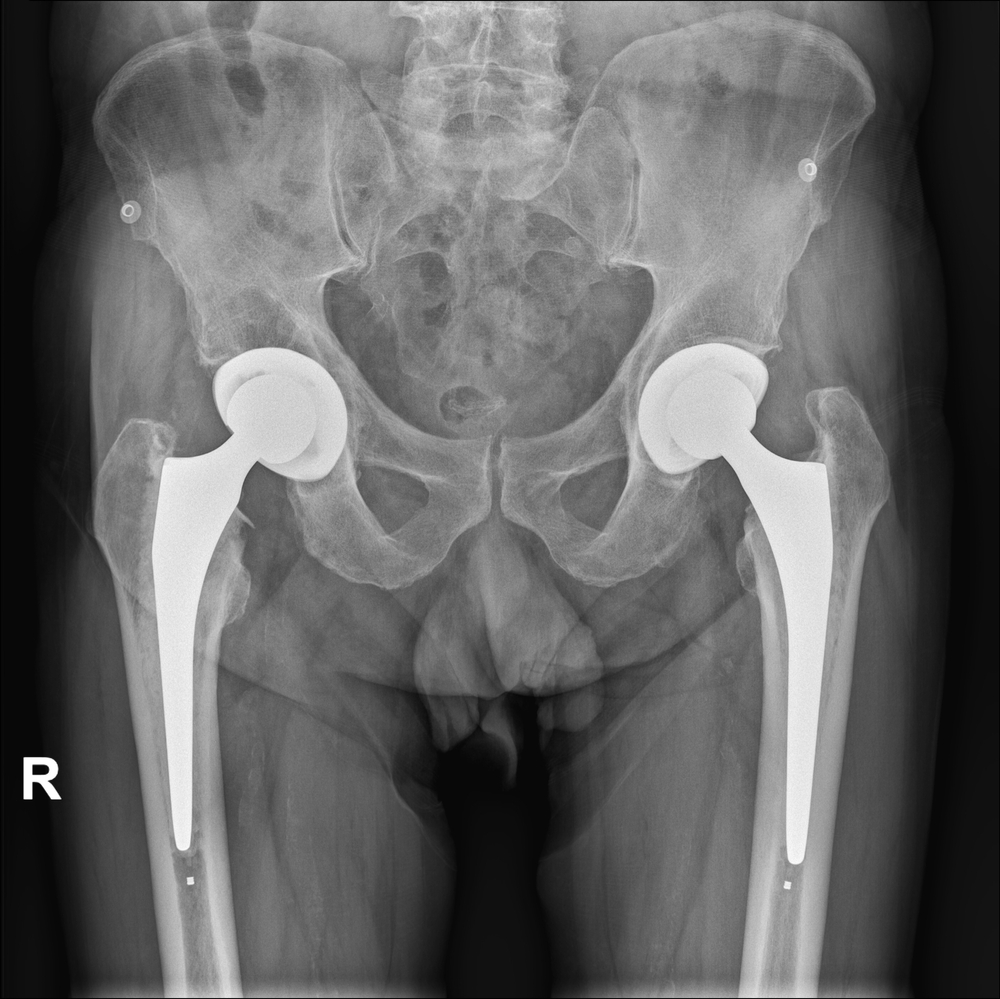

Durante l’operazione la testa del femore e l’acetabolo, cioè la cavità che la contiene, vengono sostituite con un impianto artificiale. I materiali utilizzati sono in genere leghe metalliche, ma anche la ceramica è ritenuta un materiale vantaggioso soprattutto su pazienti giovani (si tratta di un materiale più longevo) a patto che non svolgano attività traumatiche (è più fragile). Le protesi possono essere cementate o non cementate a seconda della qualità dell’osso su cui si vanno a impiantare.